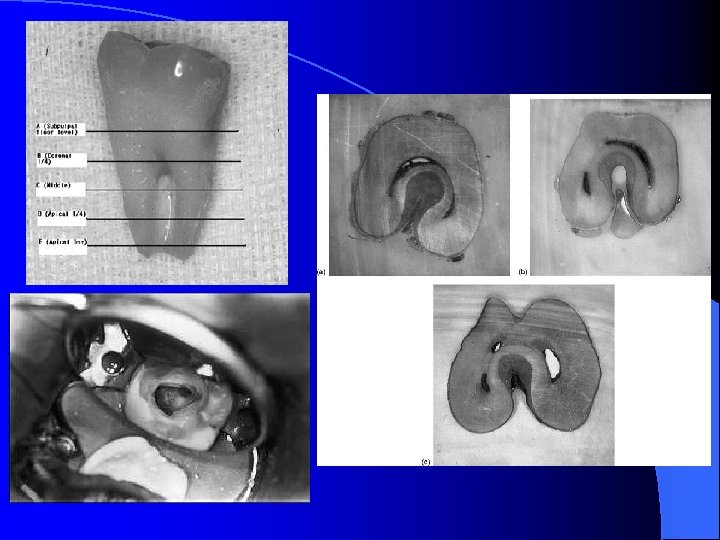

Kök ve kanal formu horizontal yönde alınan kesitte C harfine benzediği için “C şekilli molar” olarak tanımlanmıştır ve 180 derecelik yay oluşturan bir kanal girişi mevcuttur. Mezial ve distal köklerin dişin bukkal veya lingual yüzyinde birleşmesi ile oluşmaktadır. En sık alt çene 2. büyük azılarda görülmekte birlikte üst çene molar dişlerle alt çene 1. küçük azı ve 1. büyük azı dişlerde görülebilmektedir. Genelde çift taraflı görülür ve en çok Çin, Kore gibi asya toplumlarında tespit edilmiştir. Türk toplumunda görülme oranı %8. 1 olarak saptanmıştır. C kanal yapısı mezial ve distal köklerin lingual veya bukkal yüzeylerinin birleşmesi ile (füzyonlaşması) oluşur. Bu birleşmenin köklerin şekil ve sayısını belirleyen Hertwig epitel tabakasının bifurkasyon noktasında tam ayırışamamasıyla veya köklerin arasında sement birikmesi ile oluştuğu düşünülmektedir.

ALT İKİNCİ MOLAR DİŞ Ø Ø Ø Kron kısmında 5 tüberkül yerine 4 tüberkül içerir. Distal tüberkül yoktur 1. molar dişe oranla daha fazla sapmalar görülür. Mesial kökte 2 distal kökte 1 kanal bulunur. Mesial kökte tek kanal ya da 2 kanalın birleştiği şekiller görülebilir. 2 distal kanala daha ender rastlanır. Ayrıca ‘’ C ‘’ şeklinde morfoloji gösteren 2. molar dişler de olabilir. Böyle dişlerde mesial ve distal kanallara birer eğe yerleştirilerek alınan radyografide her 2 eğe aynı kanalda izlenir. Bu tip vakalarda kanal oluşumu sırasında çoğu kez aralarında geçit olduğu görülmektedir.